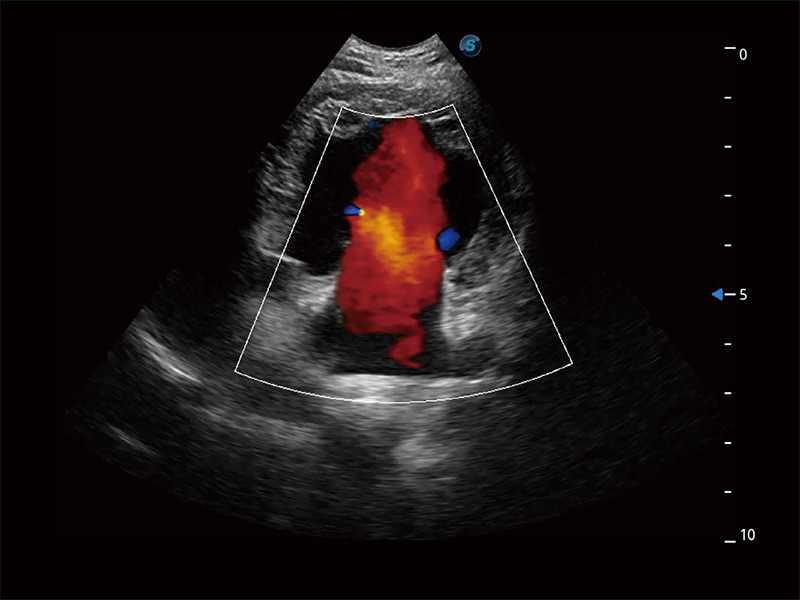

極大提升超低速微細(xì)血流的檢出能力,同時更精準(zhǔn)地濾除軟組織和超聲信號,為獸用醫(yī)生提供以往無法通過常規(guī)血流獲得的疾病診斷信息。

在傳統(tǒng)二維血流成像的基礎(chǔ)上,呈現(xiàn)血流的立體感,具有動感的生命力之美。即便是微小的血管也能輕松應(yīng)對,提高了血流的視覺敏感性。